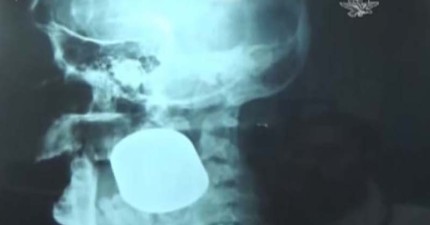

墨西哥這位女攤販經歷了一場意外,結果卡在臉上的東西連醫院都不知道是什麼…?